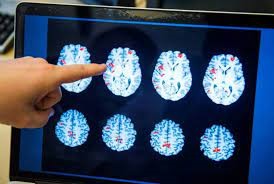

| L'activité cérébrale d'un patient mise en évidence par scanner à l'hôpital Huddinge à Stockholm, le 15 avril 2016. |

| Photo : AFP/VNA/CVN |